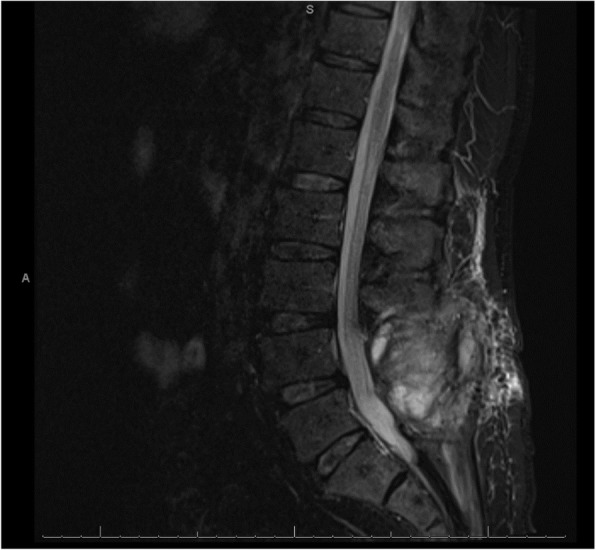

A 56-year-old Caucasian man underwent an uncomplicated elective lumbar laminectomy for spinal stenosis, after which he developed a postural headache. Due to 2 months of ongoing post-laminectomy headache, a lumbar MRI was obtained that demonstrated increased extradural fluid around L4-L5 which did not clearly communicate with the thecal sac (Fig. 1). A CSF leak was suspected, and the patient was referred for an epidural blood patch. Prior to the blood patch, 3 mL of 1% lidocaine was injected for local anesthesia. The level of L5-S1 was found utilizing fluoroscopic guidance and 1 mL of Iohexol with intrathecal-like spread noted. Then, the blood patch was performed using 20 mL of autologous blood and a 20-gauge 3.5 in. Tuohy needle, utilizing loss-of-resistance technique.

Fig. 1.

Non-contrast 1.5 T MRI STIR sequence of the lumbar spine, taken after surgery and prior to the blood patch procedure

Computed tomography (CT) of the head without contrast (Fig. 2) was obtained just under 12 h after blood injection. This imaging was remarkable for diffuse cortical sulci obscuration, with preserved grey white matter differentiation. Non-contrast 1.5 T magnetic resonance imaging (MRI) of the brain (Fig. 3) was obtained about 14 h after blood injection. On T2 fluid-attenuated inversion recovery (FLAIR), there was diffuse sulcal and ventricular hyperintensity consistent with diffuse spread of blood products or inadequately subtracted CSF. On susceptibility weighted imaging (SWI), there was diffuse susceptibility artifacts. This imaging was consistent with diffuse infiltration of blood products throughout the CSF. Additionally, MRI of the lumbar spine showed T1 hypointensity and T2 hyperintensity in the epidural and subarachnoid space, with T2 blooming artifact in the thecal sac. Lumbar spine imaging was consistent with blood products in both the epidural and subarachnoid spaces, possibly from mixed intrathecal and epidural blood injection, without hematoma.